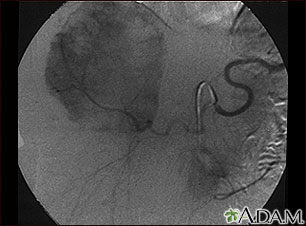

Este angiograma (una radiografía tomada después de inyectar un medio de contraste en el torrente sanguíneo) muestra una masa de vasos sanguíneos (hemangioma) en el hígado.